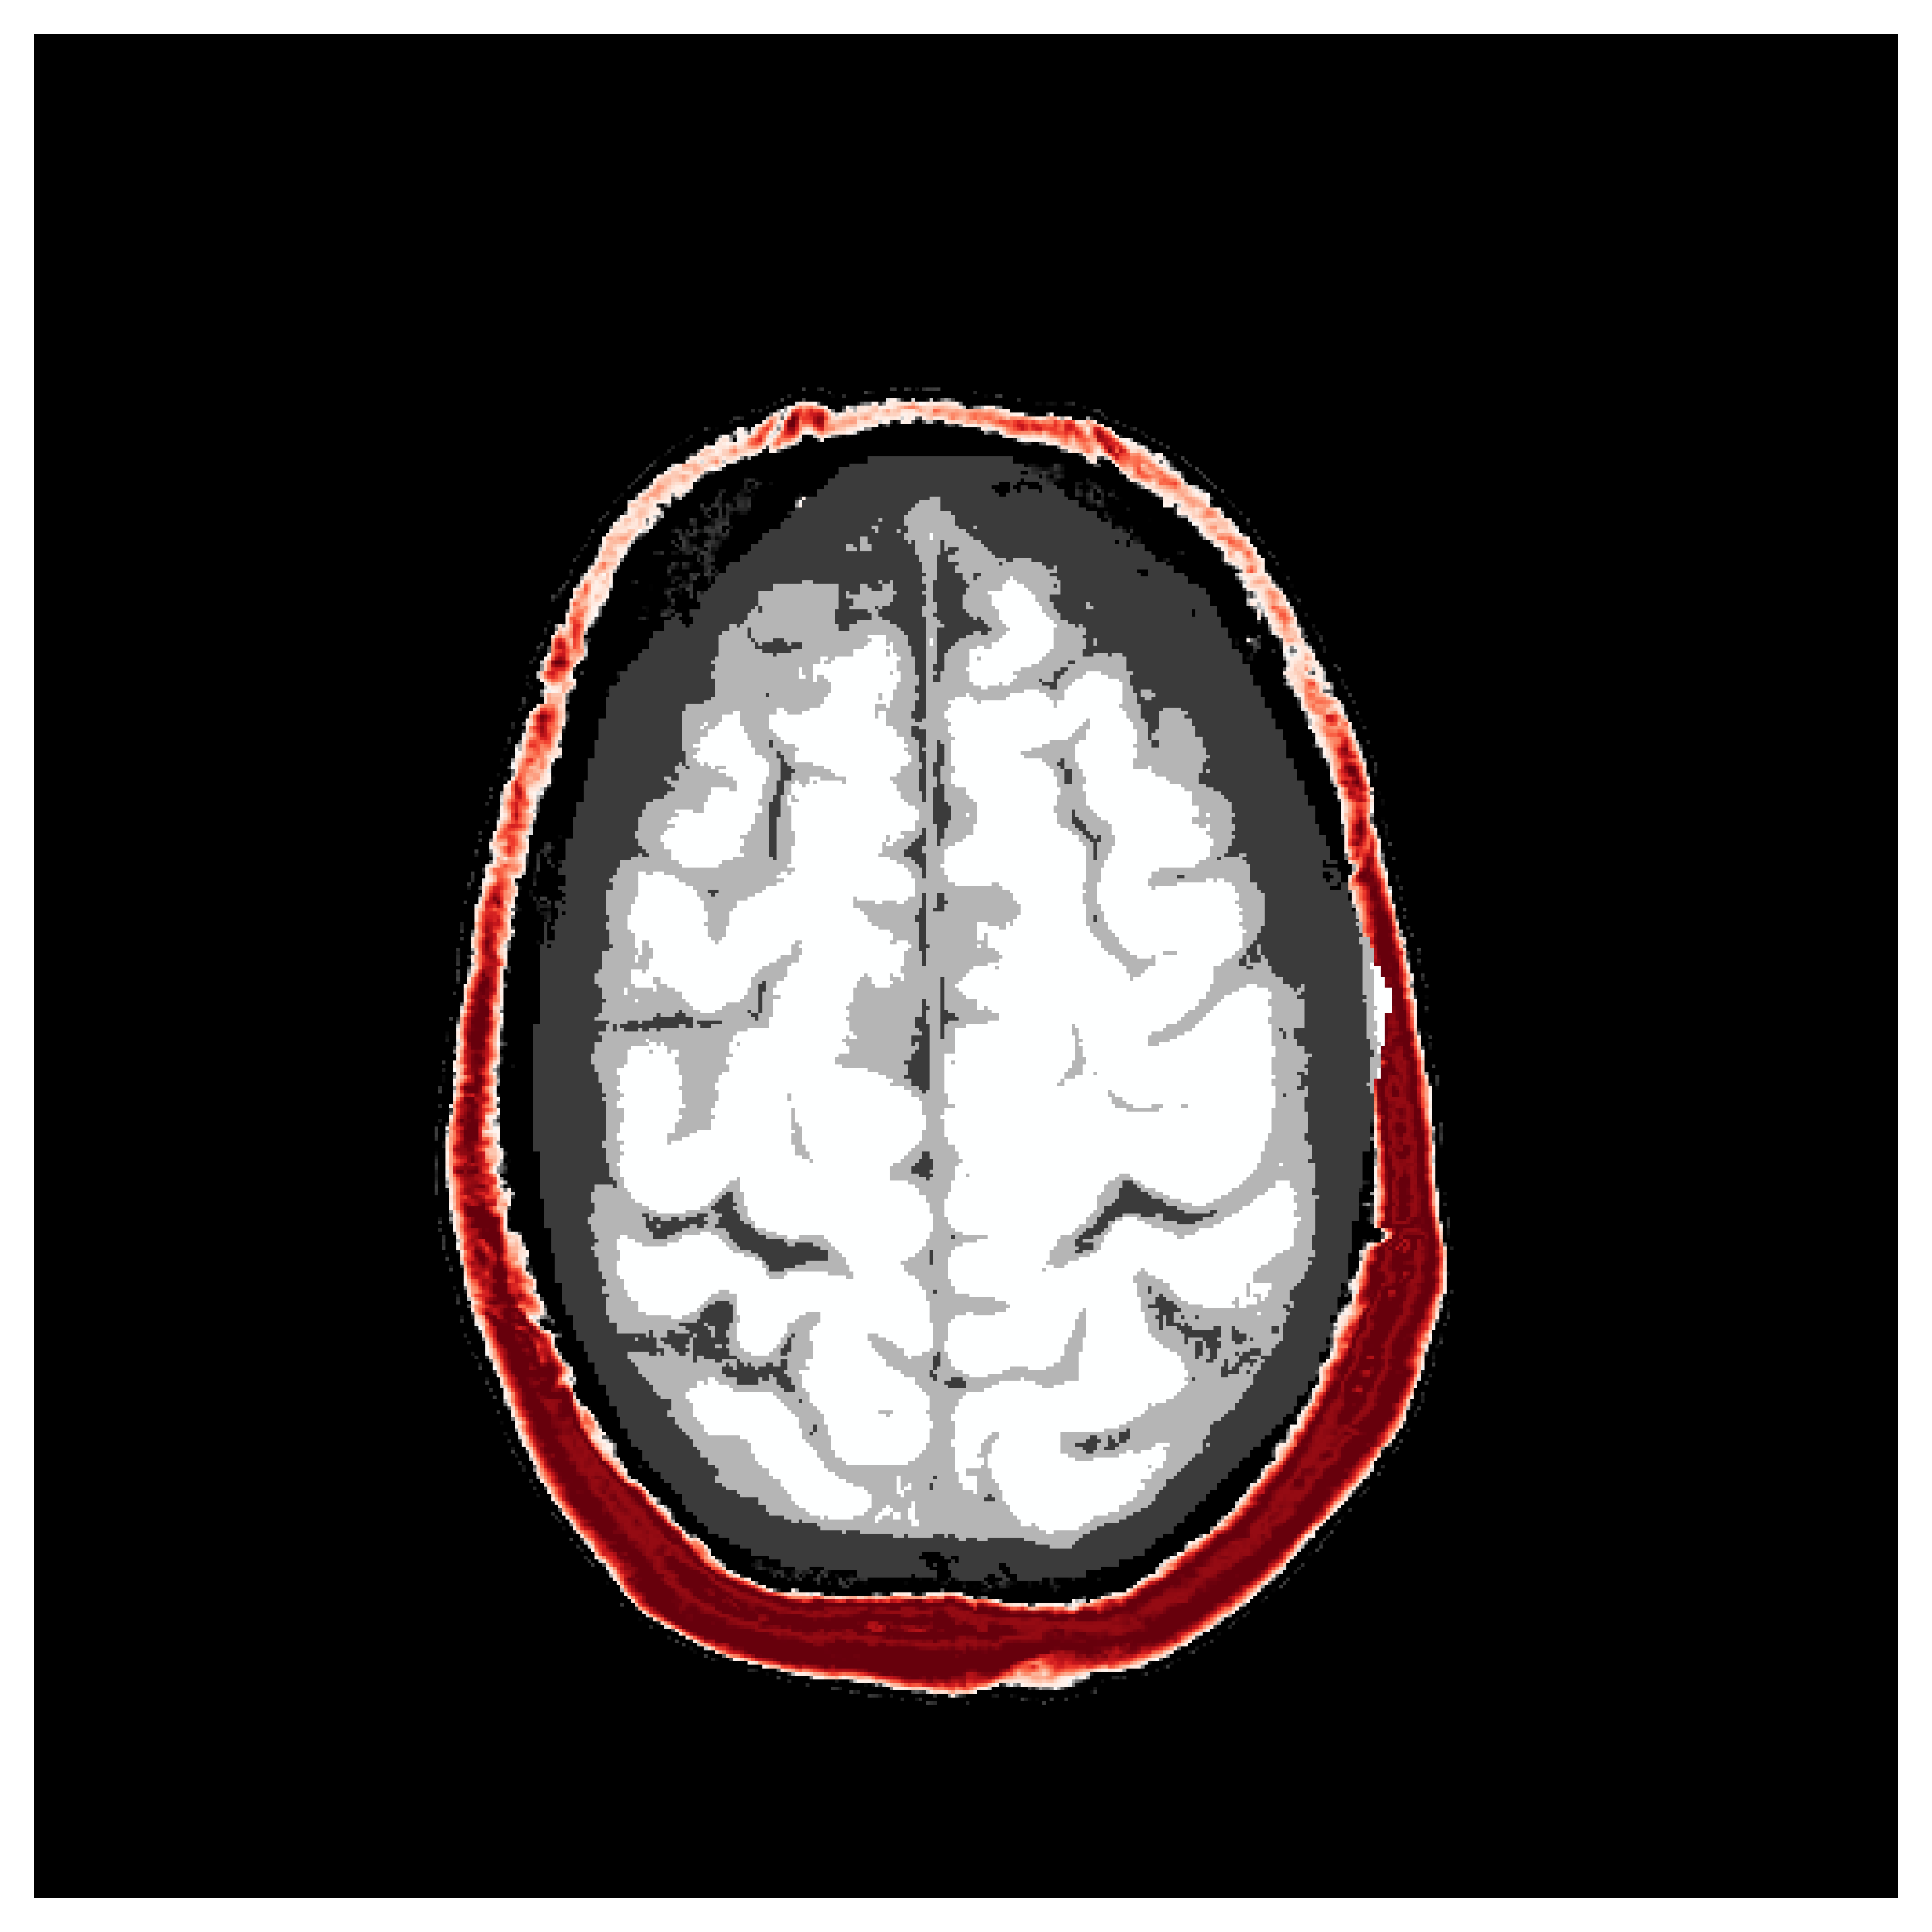

Based off of the MRI dataset [57], we manually assigned acoustic values to MRI intensities by following the table of acoustic brain tissue properties in the supplemental section of [47]. Although MRI intensities are not necessarily related to acoustic tissue properties, we found that we could produce reasonably realistic acoustic parameters as compared to the acoustic parameters from the MIDA volume. In Figure 19, we show some example training acoustic parameters. We also plot the average and standard variation between all 1000 training samples in Figure 20. From these plots, we note that there are few similarities between training examples apart from the biologically consistent human brain structures.

Appendix \thechapter.A FASTMRI acoustic dataset creation